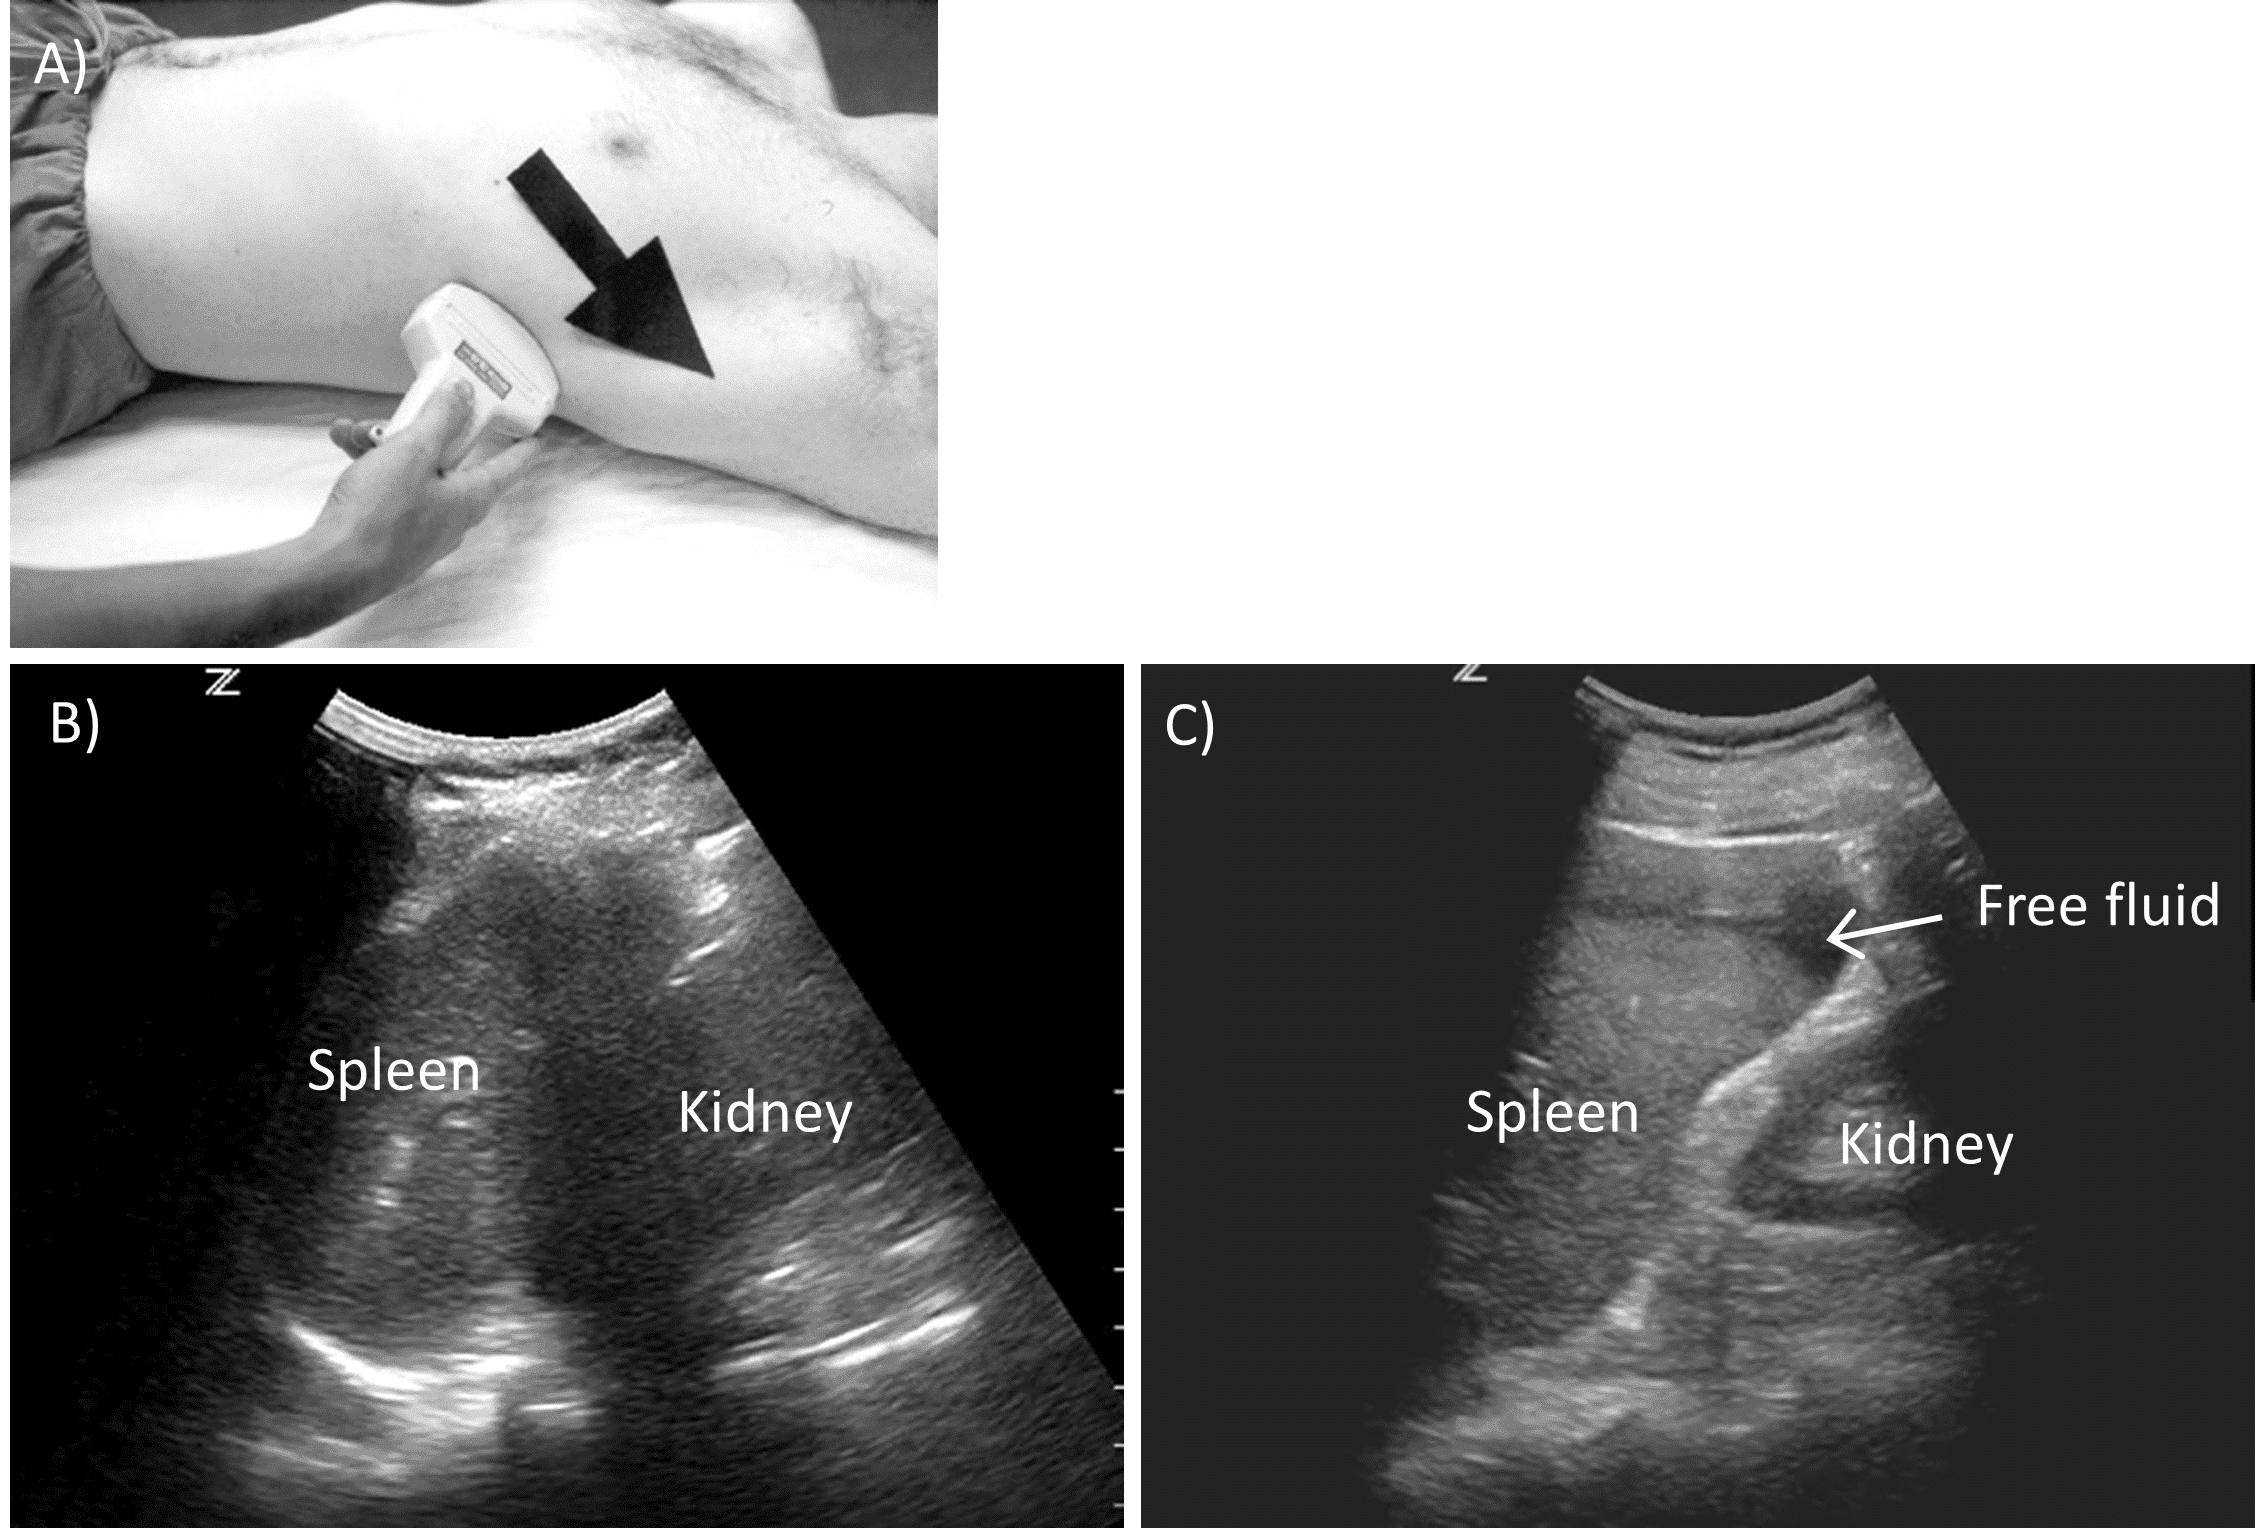

This view is used to visualize the splenorenal recess. On the left, the spleen sits more posteriorly and superiorly than the liver does on the right. Therefore, the left flank is visualized by placing the probe more posteriorly on the posterior axillary line, typically at the 8th or 9th rib space, with the indicator pointed towards the patient’s head. The probe is again fanned anteriorly and posteriorly (Figure 6).

Left Flank View.

A) Probe positioning. B) Normal view. C) Positive view with free fluid.

It is important to visualize the spleen and the kidney at the same time to prevent missing dependent fluid collections. Rib shadowing is also a challenge in this view and may be managed in a similar fashion to the right flank view, noting that the probe should instead be rotated clockwise to lie parallel to the ribs. The area posterior and superior to the spleen, beneath the diaphragm, should also be evaluated. Examining this area can enhance the sensitivity of this test, as blood can pool in this area first depending on patient anatomy.